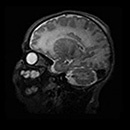

La perfetta soluzione per l’imaging neuro neonatale

Embrace® è il primo sistema MRI neonatale dedicato approvato da FDA 510 (k) e CE, progettato specificamente per l’uso all’interno dell’unità di terapia intensiva neonatale. I neonati possono essere scansionati in qualsiasi momento, entro pochi minuti dalla richiesta, per fornire informazioni critiche per una diagnosi e un trattamento più rapidi, riducendo i rischi spesso associati al trasporto fuori dall’unità di questi pazienti critici e preziosi.

le dimensioni molto contenute del magnete ne consentono l’installazione direttamente all’interno della terapia intensiva neonatale ed il gantry di dimensioni ridotte, consentono anche con un campo di “solo” 1 Tesla, un rapporto segnale rumore estremamente alto; paragonabile alle RM da 3 tesla.